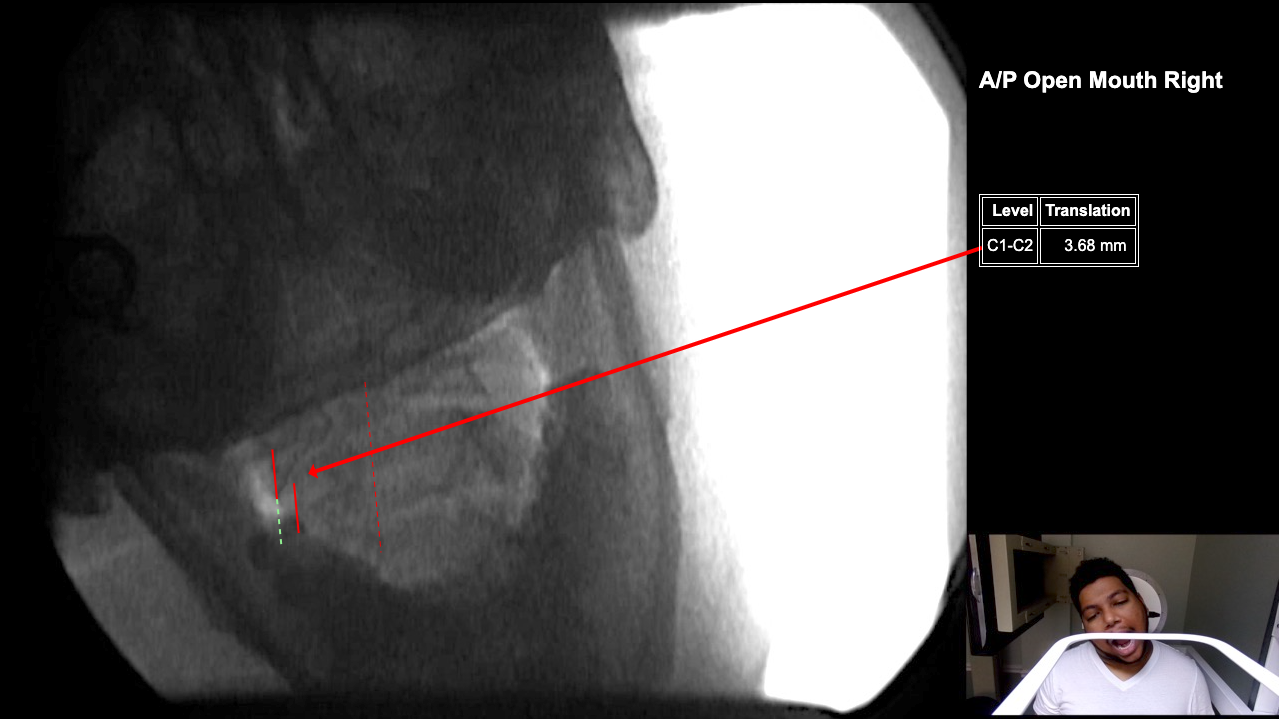

Image Name Image Type Image